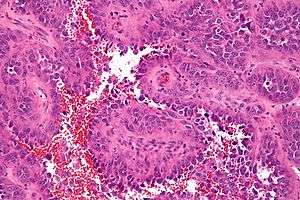

Micrograph of an angiosarcoma. H&E stain. | |

Because the cancers are carried by the blood flow or lymphatic flow, they can more easily metastisize to distant sites, particularly the liver and lungs. Most tumors of visceral blood and lymphatic vessel walls are cancerous (malignant). Hemangiosarcomas and lymphangiosarcomas of the skin are not common. Kaposi's sarcoma is a different type of cancer that also involves endothelial-type cells. Angiosarcomas will show signs of hemorrhage and necrosis. Pathologically, tumor cells will show increased nuclear to cytoplasm ratio, nuclear hyperchromasia, nuclear pleomorphism and high mitotic activity will be observed.[1]